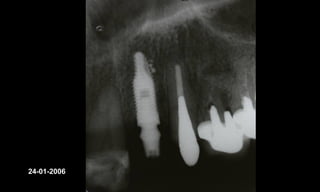

10-10-2005

Novembro de 2005

24-01-2006

Cone Morse